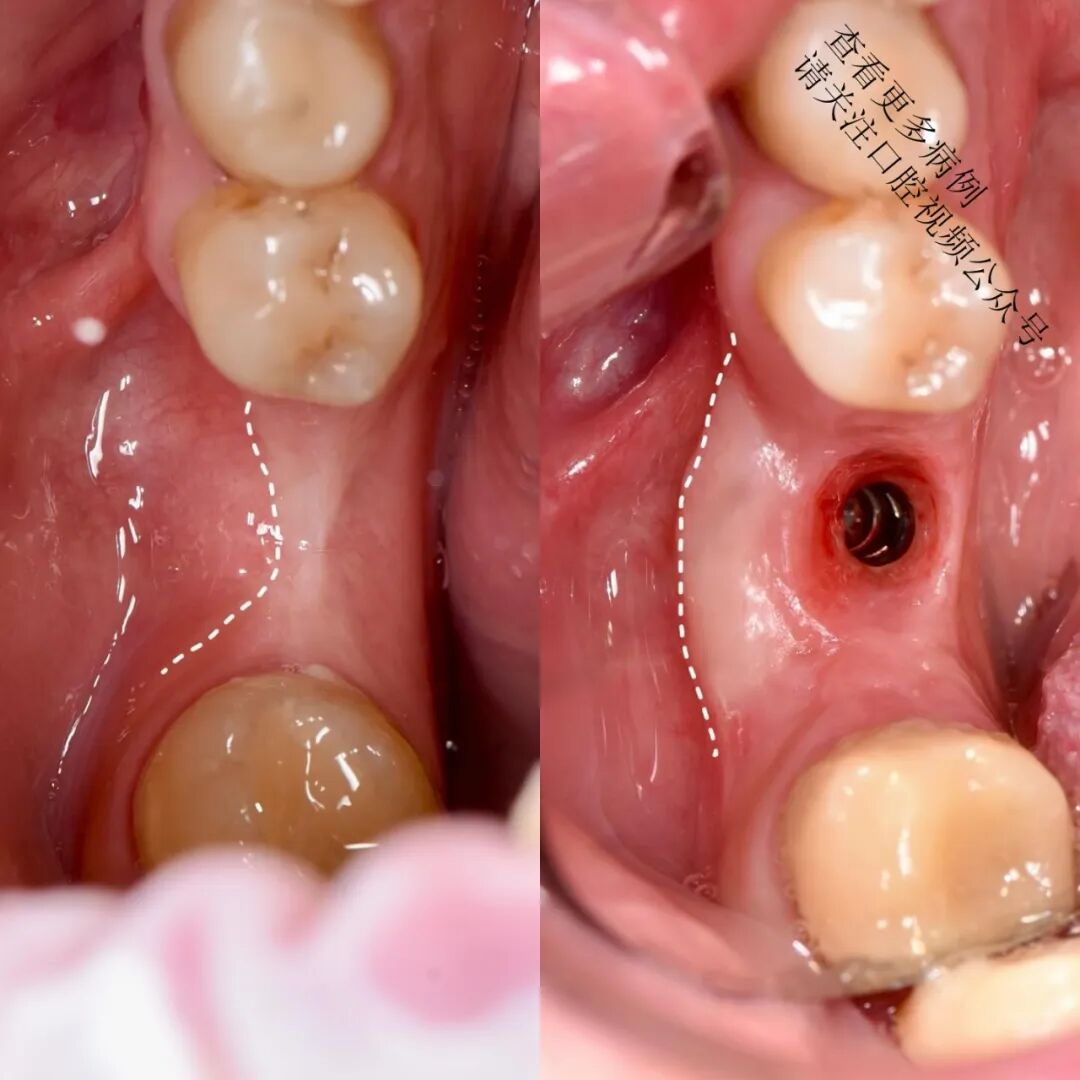

根向复位瓣术

翻制半厚瓣,去除肌肉纤维牵拉

将可移动黏膜固定至根方骨膜(使用6/0单丝缝线,如Monocryl)

术后4个月复查